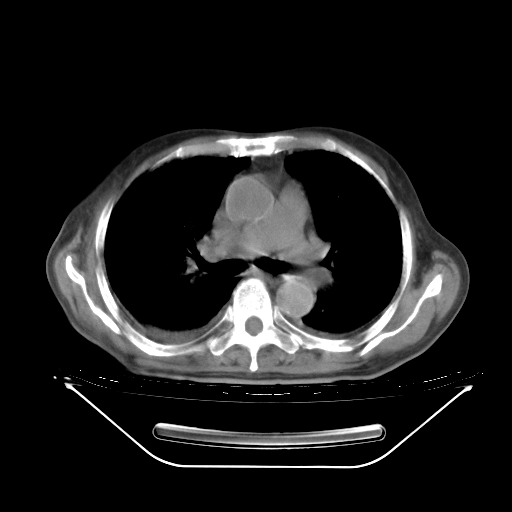

今天复查肺部CT,发现双肺广泛磨玻璃样改变。所以我把3月19日和5月9日相隔50天的肺部CT上传。请大家会诊。

5月9日肺部CT(在4月27日齐鲁医院肺部CT描述部分肺组织磨玻璃样改变,12天后肺组织广泛磨玻璃样改变)

2009年5月9日肺部CT

大致读了系列胸部CT:纵隔窗无明显异常,肺窗:从4、27至今:主要是双肺中下野外带可见毛玻璃样改变,目前处于急性肺泡炎阶段,至于原因考虑1、结替组织或胶原血管性疾病所致?2、恶性疾病如恶组在肺部所致的表现或细支气管肺泡癌?3、药物或其它原因如肺蛋白沉着症所致肺泡炎目前不太可能?总之,明天就去请我院的呼吸科、感染科、血液科和临免专家会诊哈。